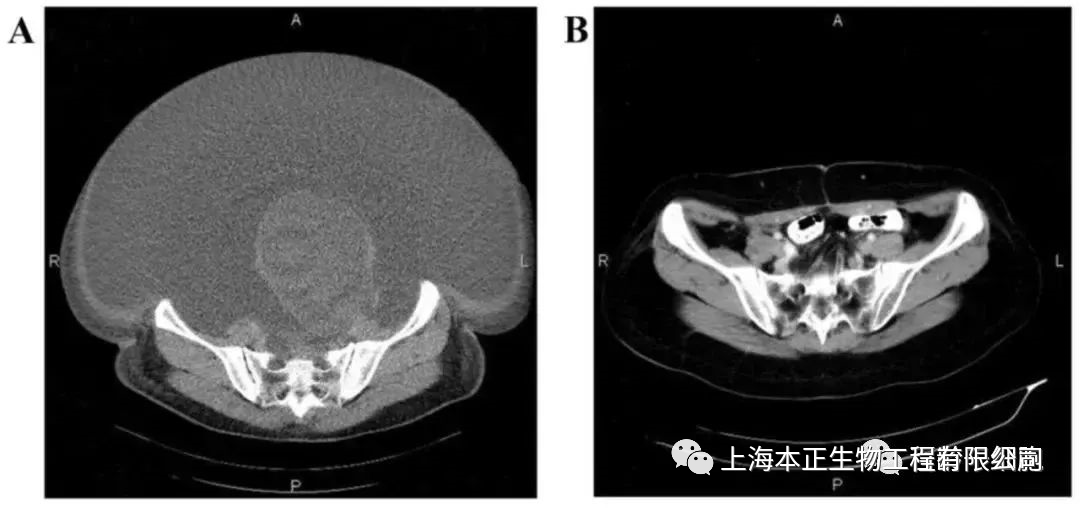

2、卵巢癌晚期患者见证NK细胞神奇疗效

根据文献报道的案例,国内第一例接受NK细胞治疗的卵巢癌患者,是一名60岁的患者,在2015年确诊为晚期,伴有大量腹水和巨大肿瘤,在接受了体外扩增,高度活化的同种异体NK细胞的治疗后,CA125水平从11,270降至580,所有腹水都消失了。此外,CT扫描的肿块体积减小,并且没有出现副作用。